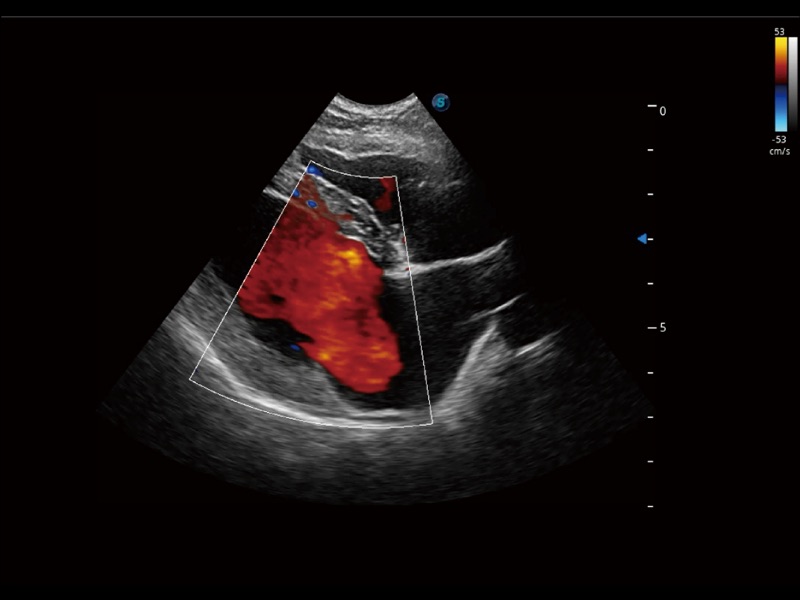

通過創(chuàng)新的 Matrix E自適應(yīng)濾波器和超長(zhǎng)時(shí)間域算法,極大提升超低速微細(xì)血流的檢出能力,同時(shí)更精準(zhǔn)地濾除軟組織和噪聲信號(hào),為獸用醫(yī)生提供以往無法通過常規(guī)血流獲得的疾病診斷信息。

通過色彩血流和實(shí)時(shí)寬景相結(jié)合,可觀察到完整的靜脈或動(dòng)脈的血流,方便醫(yī)生檢查。實(shí)時(shí)掃查過程中,如有任何操作失誤也可以很容易地進(jìn)行回掃擦除,而不會(huì)中斷掃查。